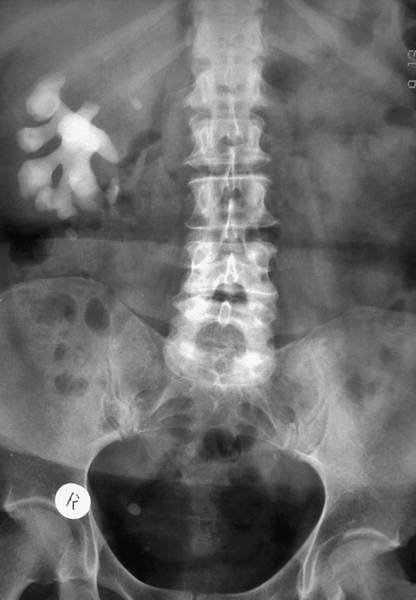

Любую тень, имеющую ту или иную степень плотности и находящуюся в зоне расположения мочевыводящих путей, необходимо трактовать как тень, возможно имеющую отношение к последним («тень, подозрительная на конкремент»). По одному обзорному снимку нельзя уверенно диагностировать МКБ. Исключение составляют лишь коралловидные камни, являющиеся слепками почечной лоханки и чашечек (рис. ). Поскольку ни в одном другом месте организма камни такой формы образоваться не могут, то при наличии коралловидного камня на обзорном снимке можно уверенно установить диагноз.

Обзорный снимок органов мочевой системы: коралловидный камень правой почки.